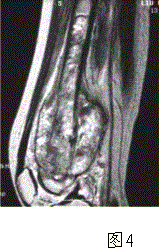

问题 患者男,16岁,左大腿下部疼痛伴肿胀2个月,逐渐加重。自感左膝上方胀痛,尤以夜间为著,伴行走困难。既往史及家族史无特殊。查体:左大腿下部明显肿胀,皮温较对侧升高。碱性磷酸酶明显增高。股骨平片及MRI见下图。 应该首先考虑的诊断为

选项 A.急性化脓性骨髓炎 B.骨结核 C.骨肉瘤 D.畸形性骨炎 E.骨转移瘤 F.软骨肉瘤

答案 C